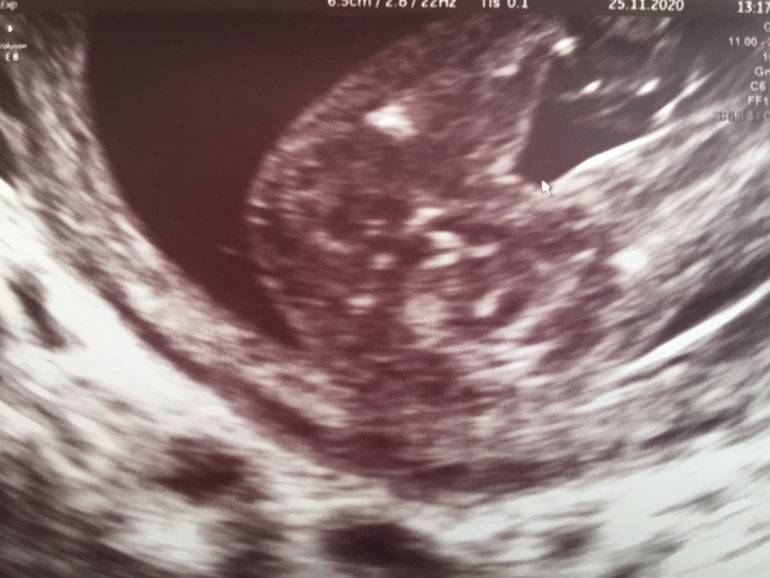

Но потом дома села снимки смотреть (ниже) и половой бугорок какой то слишком торчащим показался. Первое фото это снизу между ножек, сказали половые губки, а вот второе фото сбоку половой бугорок, он разве не мальчуковый? Срок 16.4